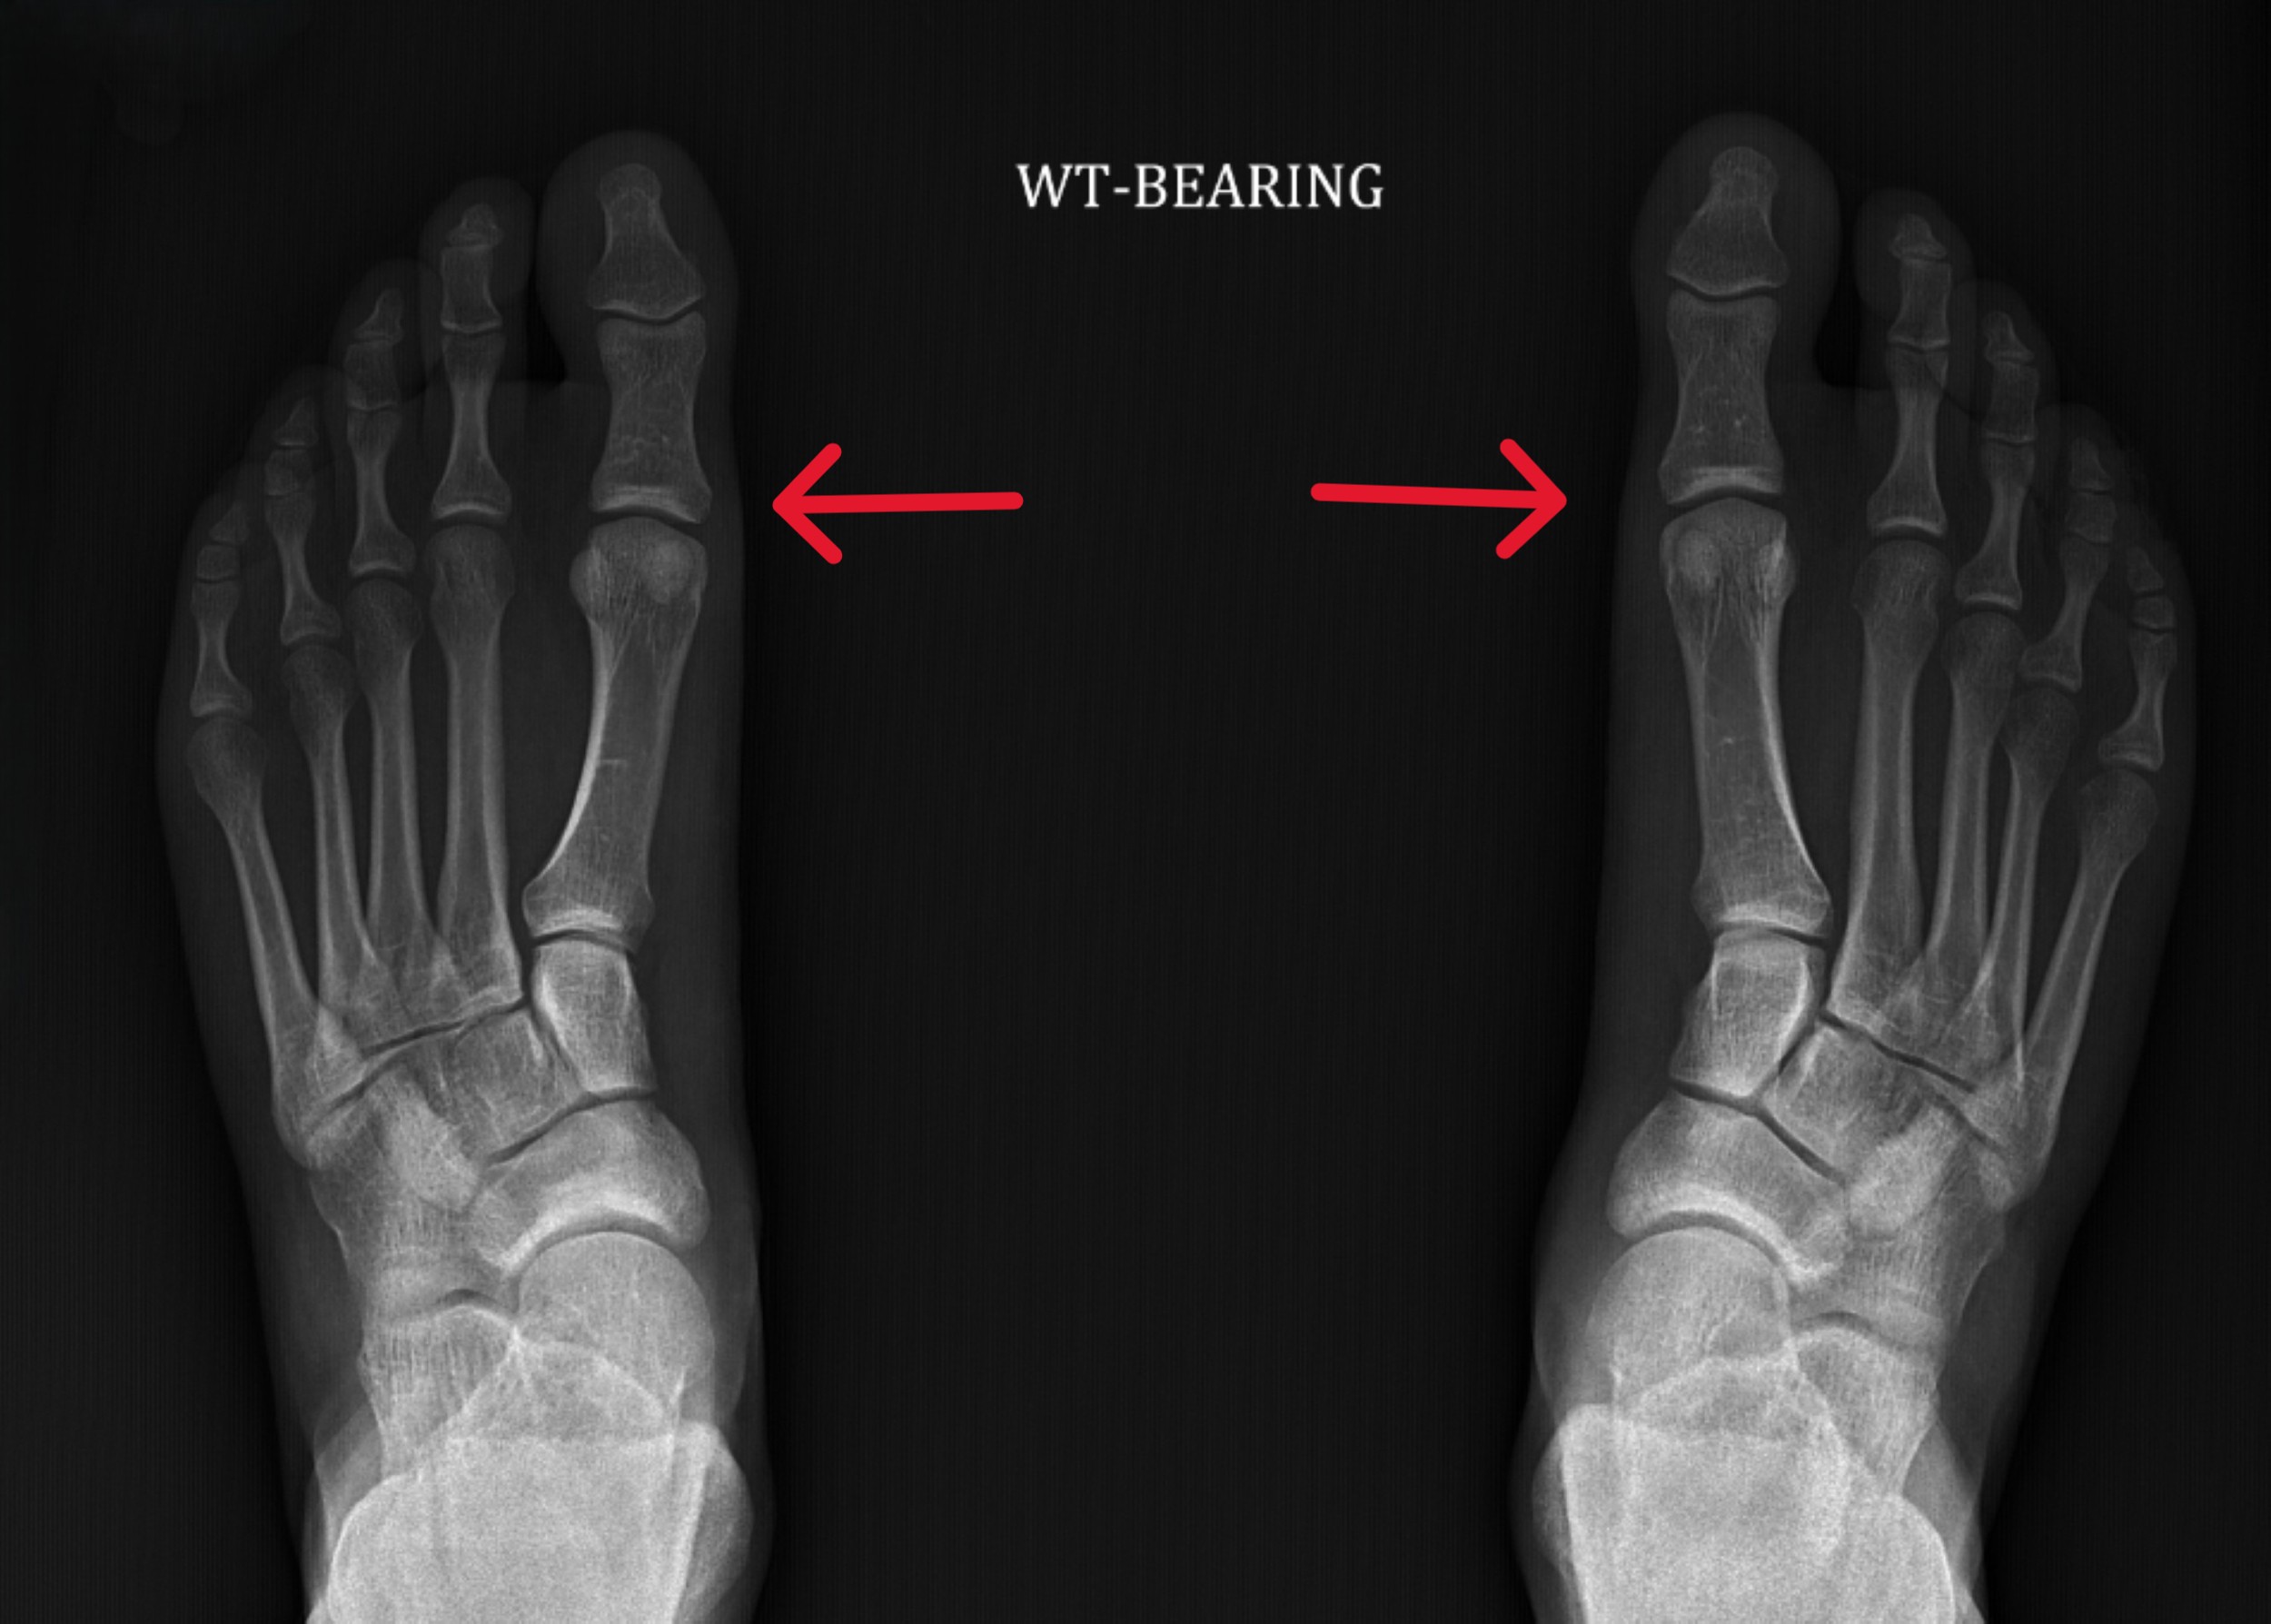

X-ray showing bones in healthy feet with arrows pointing to MTP joint

The arrows on this X-ray of healthy feet point to the metatarsophalangeal (MTP) joints that are the focus of turf toe injuries.

Turf toe is another name for a metatarsophalangeal (MTP) joint sprain. Your toe has two big joints, the larger of which is the MTP joint that connects the base of your big toe to the rest of your foot. It is surrounded by soft tissues such as ligaments and tendons. Turf toe occurs when your toe is hyperextended – or bends farther than it’s supposed to – causing the soft tissues in your big toe to stretch or tear.